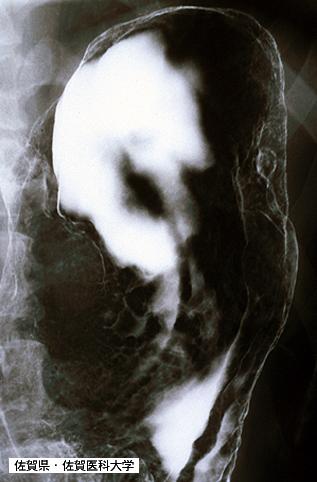

위와 대장에 다발병변을 보인 성인T세포 백혈병(ATL) (증례제시:사가의과대학、Dr.미즈구치)

Saga Pref., Saga Medical School (Saga Medical School)

[Image-ID:3646]

악성 림프계종양 및 혈액계종양/ATL(성인 T세포백혈병)

부위(장기별)

위(부위)/체부

검사방법

X-P

종양의 최대경(밀리미터)

25~29

다발종양(동일 장기)

유(동시성)

다중종양(다수의 장기)